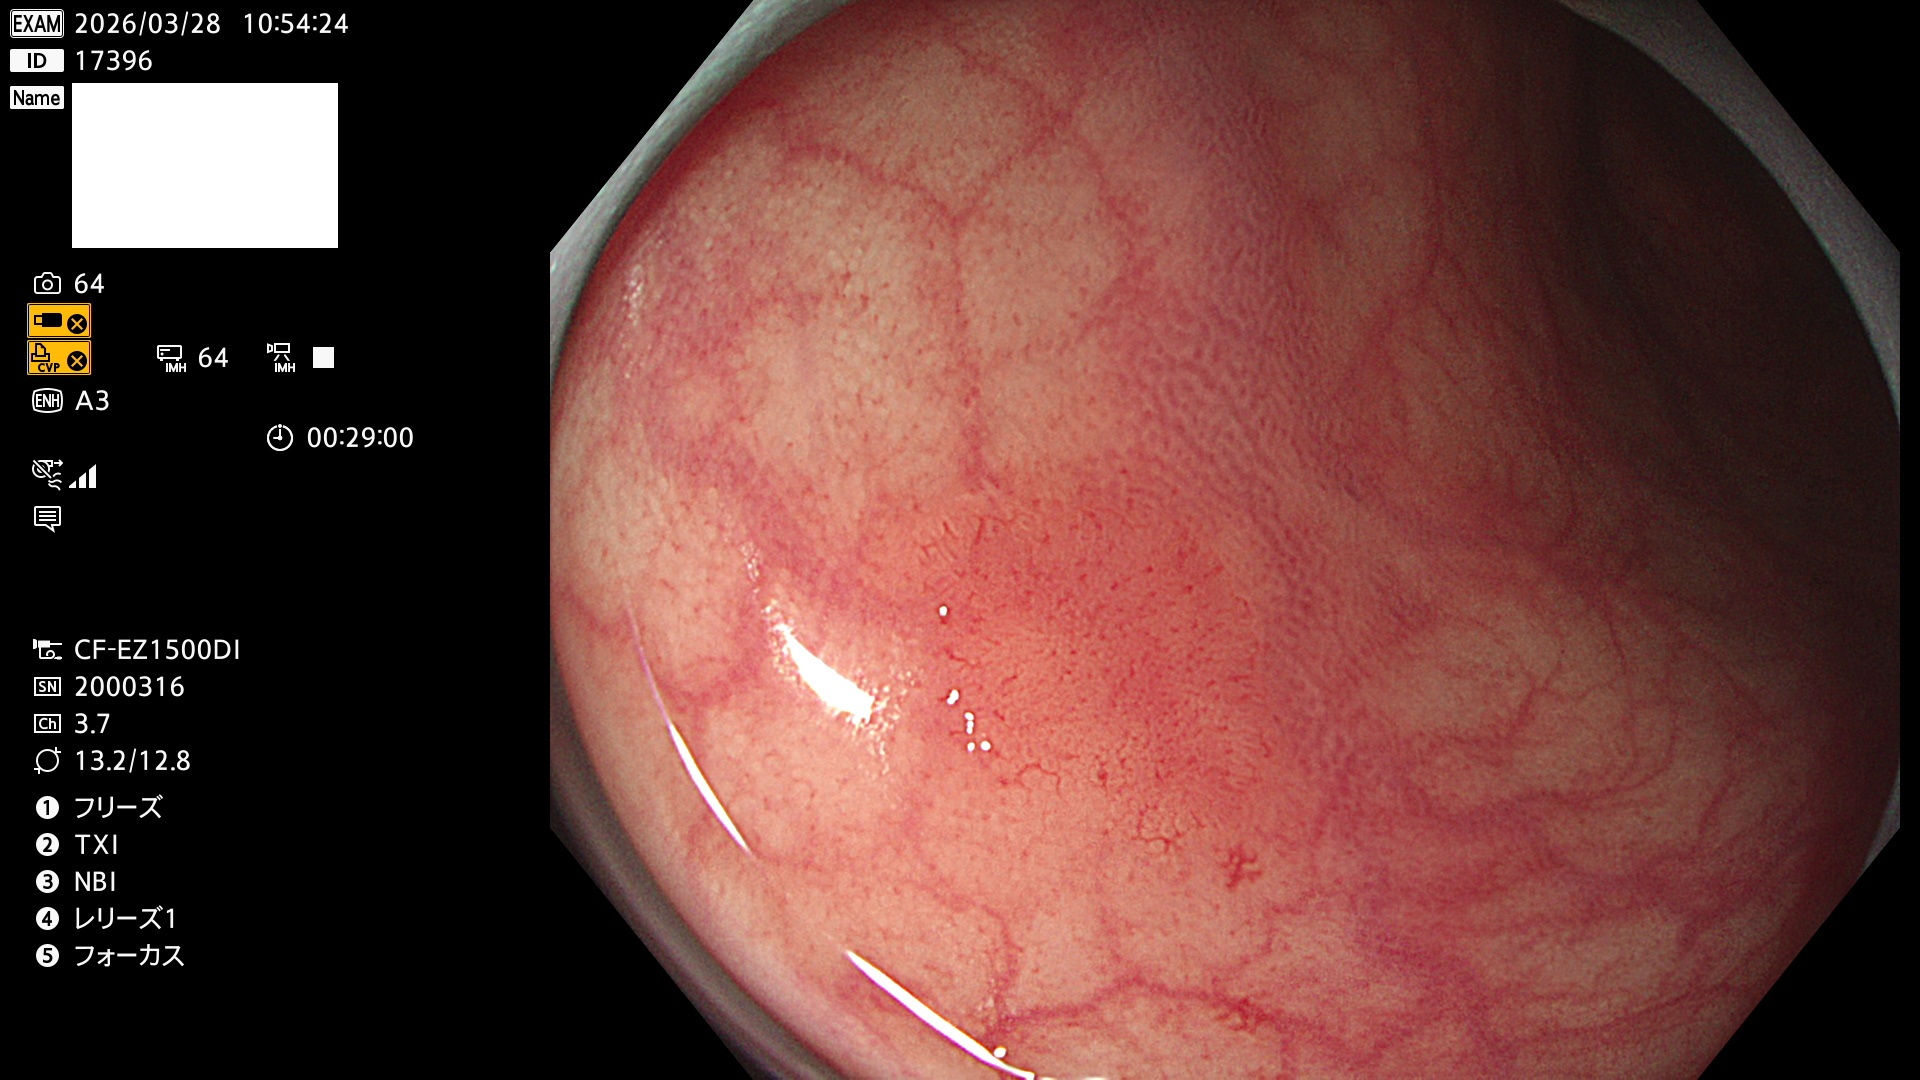

毎週の検査(木・金・土・日)に発見されたUbとUc型・腺腫を、その週の日曜の夜にUPし1週間、提示します。

2026年3月26日〜3月29日の4日間(40件)4個 (Uc_ADR=4個/40人=10%)